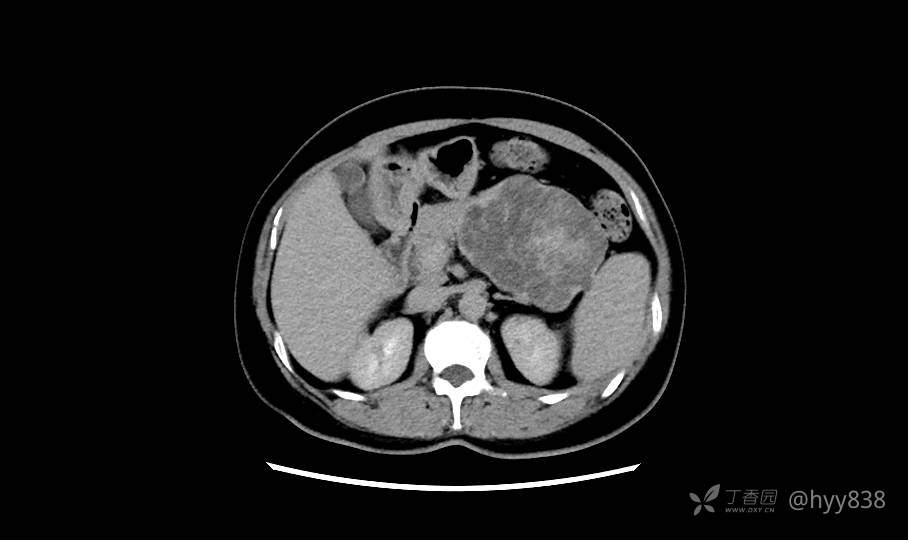

胰腺增强动脉期